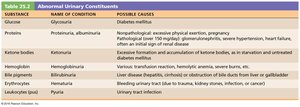

Abnormal Urinary Constituents

The presence of abnormal substances in urine can indicate disease:

Substance | Name of Condition | Possible Causes |

|---|---|---|

Glucose | Glycosuria | Diabetes mellitus |

Protein | Proteinuria, albuminuria | Excessive exertion, pregnancy, hypertension, heart failure, renal disease |

Ketone bodies | Ketonuria | Starvation, diabetes mellitus |

Hemoglobin | Hemoglobinuria | Transfusion reaction, hemolytic anemia, burns |

Bile pigments | Bilirubinuria | Liver disease, obstruction of bile ducts |

Erythrocytes | Hematuria | Bleeding urinary tract (trauma, stones, infection) |

Leukocytes (pus) | Pyuria | Urinary tract infection |

Additional info: The above table summarizes the diagnostic significance of abnormal findings in urine analysis, which is a key tool in clinical nephrology.